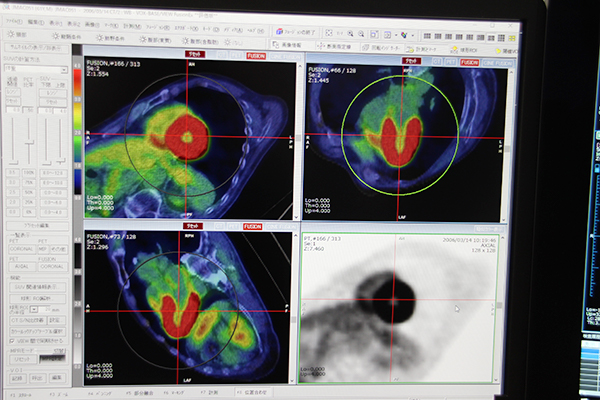

読影用統合画像ビューワ「XTREK VIEW」では,マルチモダリティ対応のフュージョンソフトウエアである“FUSION Plus”(オプション)の新機能として,VOI(volume of interest)の記録・呼び出し機能,画像再構成で断面角度を自由に変更して表示や出力できる機能が展示された。

FUSION Plusは,PET/CTだけでなく,異なるモダリティのボリュームデータのフュージョンが行えるほか,過去画像との比較がしやすいレイアウトへのカスタマイズや,検査画像の自動的な位置合わせなどが特長である。

新機能のVOIの記録・呼び出し機能は,PET画像でSUVや体積,total legion glycolysis(TLG)計測をするために設定する閾値VOIをアップデートしたもの。VOI情報を複数箇所保存し,いつでもVOIを呼び出すことができる。VOIは保存した検査画像だけでなく,位置合わせされた比較画像の同じ位置に呼び出すことができるため,SUVや体積,TLGの比較が容易になる。

また,これまでフュージョン画像の再構成では横断像など定められた断面像でしか再構成ができなかったが,断面角度を自由に変更できるようになったため,長軸像や短軸像で表示,出力することができる。

FUSION Plusの新機能では,保存したVOIを比較画像上の同じ位置にも呼び出すことができる。

VOIの中のSUVや体積,TLGを算出することが可能

画像再構成後の断面角度を自由に変更できる。